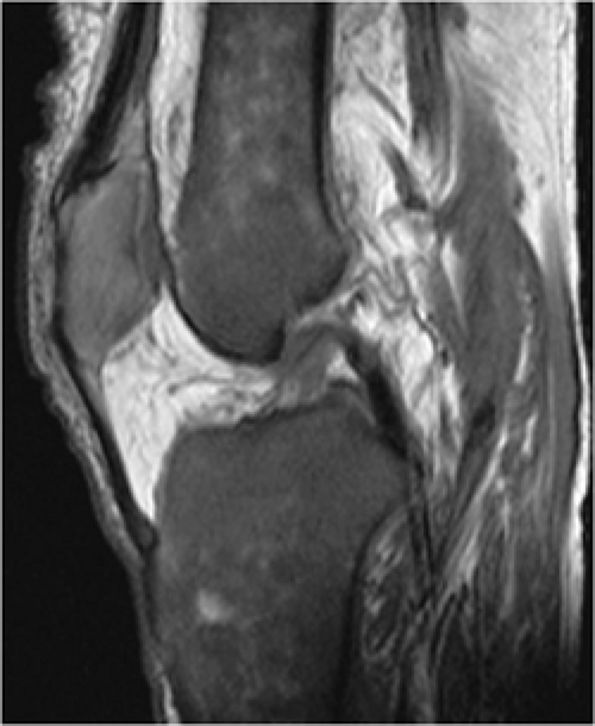

FIGURE 13.83 ● Bone marrow infarcts in a patient with sickle cell anemia. (A) On a coronal T1-weighted image through the posterior aspect of the knee, areas of osteonecrosis show low-signal serpentine lines (arrows). Fat signal intensity within the infarcted segment is demonstrated (arrowhead). (B) On a corresponding coronal STIR image, the serpentine lines are hyperintense (arrows) while the marrow within the area of osteonecrosis is dark, corresponding to fatty marrow (arrowhead).

|